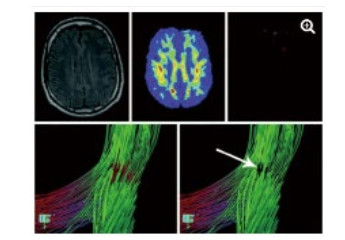

DWI利用梯度回旋技术来监测水分子弥散的难易程度,能比其他影像手段更早发现脑缺血。DTI是DWI的发展和深化, 结合FA等参数能独特显示全脑白质传导束,并且能够评估其功能的完整性。研究表明,重度脑外伤患者胼胝体膝部和压部的FA值下降,同时压部白质纤维束数量减少。这些变化不仅仅与GCS评分有关,还和患者的预后,包括认知评分显著相关[31-34]。借助DTI技术,能从形态学上解释意识障碍存在的结构基础,直观评价患者损伤程度[34](图 3)及预后[35],具有较高的精准性。在心搏骤停后昏迷患者意识评估研究中发现,DTI及FA的联合应用在预测患者预后不良的灵敏度达94%,特异度达100%[35]。

| 图 3 一例49岁TBI患者,常规MRI检查未发现明显异常(左上图)运用FA技术显示在左侧额叶白质中发现一个FA减少的区域(上中图),运用DTI显示局部纤维提示不联系(箭头所指) |